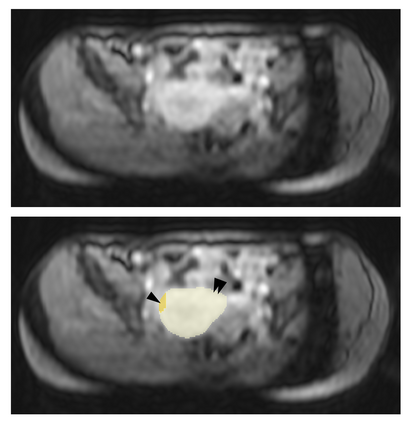

Purpose: To introduce a deep learning model capable of multi-organ segmentation in MRI scans, offering a solution to the current limitations in MRI analysis due to challenges in resolution, standardized intensity values, and variability in sequences. Materials and Methods: he model was trained on 1,200 manually annotated MRI scans from the UK Biobank, 221 in-house MRI scans and 1228 CT scans, leveraging cross-modality transfer learning from CT segmentation models. A human-in-the-loop annotation workflow was employed to efficiently create high-quality segmentations. The model's performance was evaluated on NAKO and the AMOS22 dataset containing 600 and 60 MRI examinations. Dice Similarity Coefficient (DSC) and Hausdorff Distance (HD) was used to assess segmentation accuracy. The model will be open sourced. Results: The model showcased high accuracy in segmenting well-defined organs, achieving Dice Similarity Coefficient (DSC) scores of 0.97 for the right and left lungs, and 0.95 for the heart. It also demonstrated robustness in organs like the liver (DSC: 0.96) and kidneys (DSC: 0.95 left, 0.95 right), which present more variability. However, segmentation of smaller and complex structures such as the portal and splenic veins (DSC: 0.54) and adrenal glands (DSC: 0.65 left, 0.61 right) revealed the need for further model optimization. Conclusion: The proposed model is a robust, tool for accurate segmentation of 40 anatomical structures in MRI and CT images. By leveraging cross-modality learning and interactive annotation, the model achieves strong performance and generalizability across diverse datasets, making it a valuable resource for researchers and clinicians. It is open source and can be downloaded from https://github.com/hhaentze/MRSegmentator.